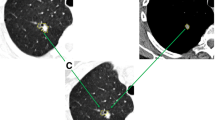

To develop a predictive model by 18F-FDG PET/CT radiomic features and to validate the predictive value of the model for distinguishing solitary lung adenocarcinoma from tuberculosis.

A total of 235 18F-FDG PET/CT patients with pathologically or follow-up confirmed lung adenocarcinoma (n = 131) or tuberculosis (n = 104) were retrospectively and randomly divided into a training (n = 163) and validation (n = 72) cohort. Based on the Transparent Reporting of Multivariable Prediction Model for Individual Prognosis or Diagnosis (TRIPOD), this work was belonged to TRIPOD type 2a study. The Mann-Whitney U test and least absolute shrinkage and selection operator (LASSO) algorithm were used to select the optimal predictors from 92 radiomic features that were extracted from PET/CT, and the optimal predictors were used to build the radiomic model in the training cohort. The meaningful clinical variables comprised the clinical model, and the combination of the radiomic model and clinical model was a complex model. The performances of the models were assessed by the area under the receiver operating characteristic curve (AUC) in the training and validation cohorts.